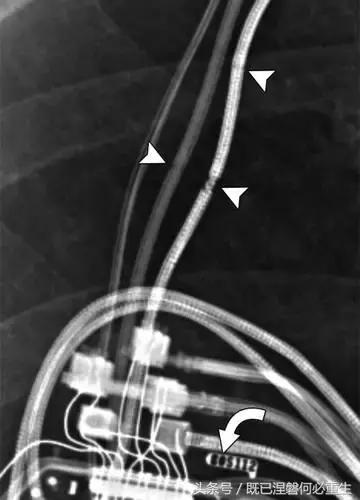

图。 7A 79岁的男性患有电极折断和迁移。

A,初始胸前X线片显示Pacesetter双腔起搏器低于锁骨的心房导线不完全断裂(变薄)(箭头)。

图。 7B 79岁的男性患有电极折断和迁移。

B,大约3年后,电极完全断裂,金属传导碎片(箭头)分离。 远端片段(箭头)已经偏移尾侧,但是由于围绕电极的射线可穿透鞘的约束效应而没有迁移到肺循环中。 引线和中心静脉导管最常见于锁骨和第一肋骨之间断裂,因为它们在臂运动期间被锁骨下肌肉或腱或肋锁韧带压缩[16]。

导致设备故障的最常见的X光检查原因之一是铅断裂。锁骨下静脉经过锁骨下的部位是骨折最常见的位置[16](图7A和7B)。在这个位置的损伤可能发生在导管或导线,并已被描述为锁骨下夹断综合征和锁骨下压溃综合征[16?18]。临床上,骨折的导线通常在患者中产生可以是连续的,间歇的或依赖于患者定位的症状。识别这些状况可能需要挑衅性的动作,例如等长臂锻炼,仰卧或侧向定位或Valsalva。设备检查将显示异常的起搏阻抗(如果绝缘破裂允许导体暴露则减小,如果导体断裂但绝缘完好则增加),感测错误和起搏捕获损失[12]。导线断裂或绝缘损坏可能导致感测或起搏异常。对心律失常的不适当的过感知或欠感应可能导致不适当的治疗,例如抗心动过速起搏和休克治疗,或不适当的抑制治疗。